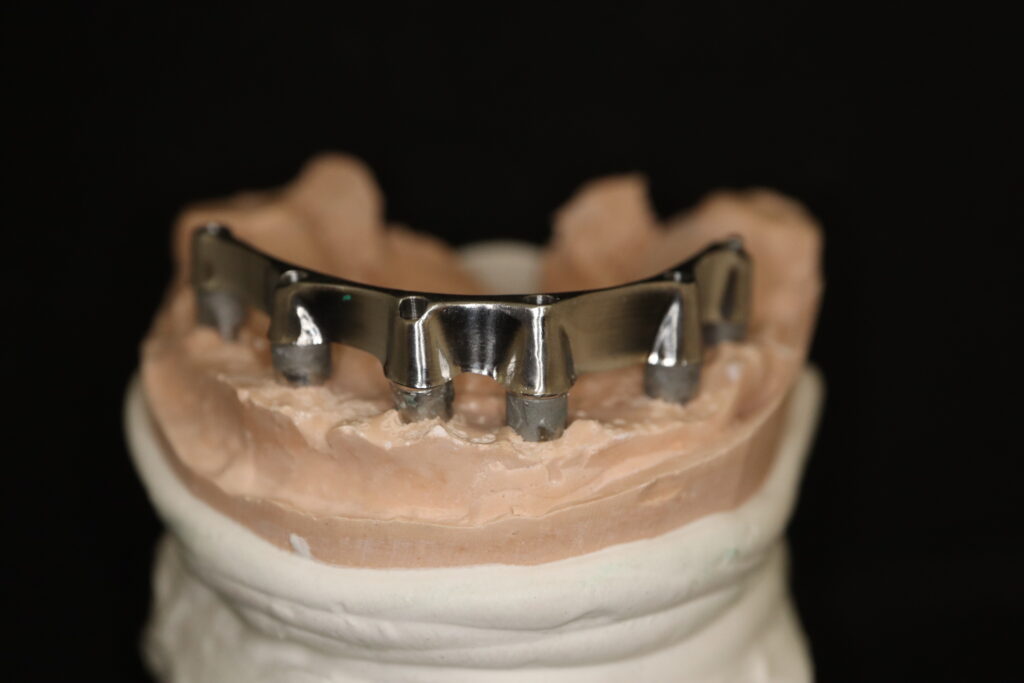

На консультации было принято решение о перепротезировании протезом из диоксида циркония на титановой балке.

Спустя 27 дней был зафиксирован протез с опопрой на дентальные имплантаты из диоксида циркония с каркасом из титана.

Пациенту были установлены 6 имплантатов Megagen AnyOne по системе All-on-6 на верхней челюсти и 4 имплантата на нижней по классической двухэтапной методике.